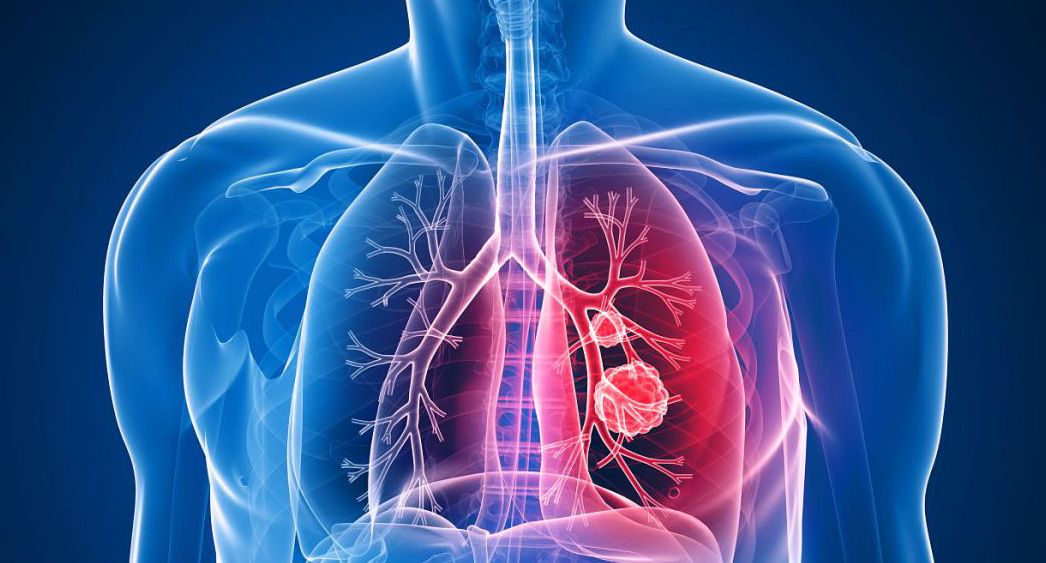

호흡 곤란은 폐암의 증상입니다. 폐암 환자의 약 4분의 1이 호흡곤란 증상을 보이며, 이는 다발성 폐 전이가 양측 증상을 나타내거나 악성 흉막삼출이 폐암과 함께 발생할 때 발생합니다. 폐암은 점차 흉통을 악화시킬 수 있으며, 폐암이 진행됨에 따라 폐암의 크기가 커지거나 그 부위에 물이 차게 되면 호흡이 흉막을 자극하여 호흡곤란과 흉통을 유발할 수 있습니다. 격렬한 작업이나 격렬한 운동을 하지 않았더라도 호흡곤란이 발생하거나 호흡이 불편한 경우 의사의 진찰을 받는 것이 좋습니다.